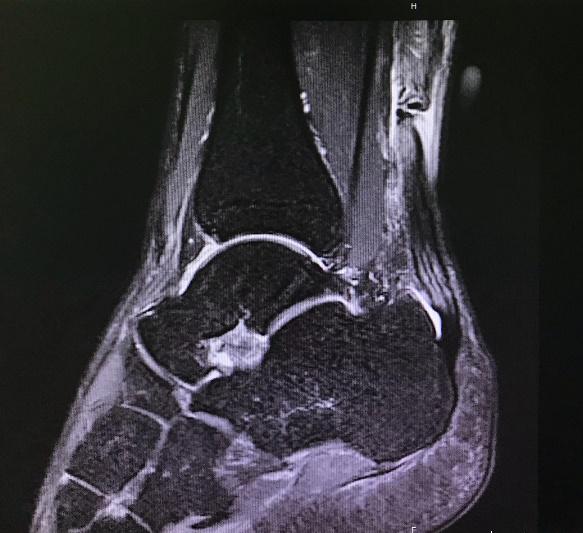

像刘翔、考辛斯、杜兰特等无数优秀运动员折梦在跟腱断裂这一问题上。 跟腱是腓肠肌和比目鱼肌汇合后延续的部分,是机体最粗、最强大的肌腱。在激烈运动中,跟腱可能承受高达 8倍体重的牵拉负荷,因此,跟腱断裂是运动创伤中较常见的损伤之一,好发于30~39岁的青壮年男性。还有研究报道,跟腱断裂的发生率为十万分之九点三。

早在1929年就有跟腱修复后再断裂的并发症进行了报道。,Qenu等第一次对大宗再断裂病例采用手术和非手术两种治疗的效果进行了对比分析。此后有关各种治疗风险和益处的争论一直在激烈的进行。分析再断裂发生的几个原因中,最重要的是修复肌腱的纤维瘢痕组织的力学强度不如正常的跟腱组织。从而会在两种条件引起瘢痕再断裂,一是单次*力暴**牵拉超过了瘢痕组织所承受的最大强度导致肌腱断裂;二是日常生活对瘢痕组织反复的低强度的牵拉作用,导致肌腱疲劳断裂。所以在重建术后以及康复过程中要多加小心防止跟腱的再断裂。